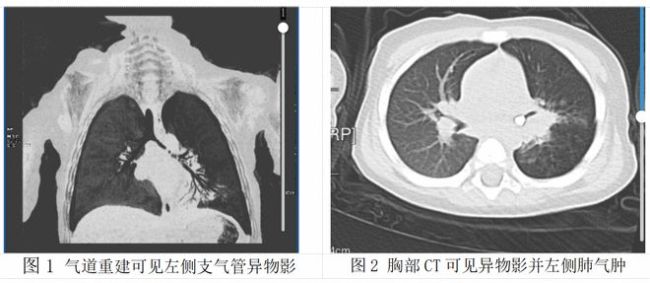

在外院完善CT检查后(图1-2),真相终于浮出水面:孩子左侧支气管内,牢牢卡着那颗乳牙!异物长期堵塞气道,易引发严重的肺部感染、气道水肿,病情极其凶险。更让救治难上加难的是,因长期患病、营养摄入不足,宝宝还合并中度贫血,血红蛋白仅80g/L,身体耐受度极差,这也让后续的手术和麻醉风险成倍增加。

时间就是生命,家属紧急将孩子转至北京儿童医院接受专业救治。面对贫血、感染、气道梗阻三重高危因素,患儿的麻醉风险远高于普通儿童,稍有不慎就可能出现缺氧、循环波动、窒息等危险情况。万幸的是,在经验丰富的麻醉团队精准监护、精细操作下,为手术搭建起坚实的“生命安全防线”,最终医生在全麻下顺利完成气管异物取出术,将滞留气道50天的牙齿成功取出(图3),孩子有惊无险渡过难关,目前正逐步恢复健康。